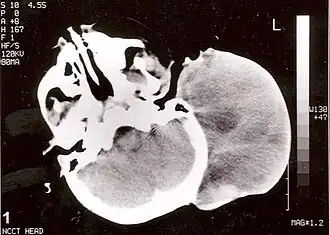

Rabdomiossarcoma (RMS) é uma variedade de sarcoma que afeta o tecido muscular esquelético, originando-se de células mesenquimais[1]; um tipo de câncer que se desenvolve a partir de células musculares chamadas rabdomioblastos que geralmente afeta crianças e adolescentes, sendo um dos tipos mais comuns de câncer infantil.